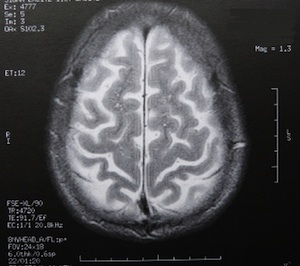

Sie sind hier: Startseite Nachrichten Wissenschaft „BrainNet“ hat Köpfe erfolgreich vernetzt: Kommt jetzt das Internet der Gehirne? Bild: pixelio.de/Dieter Schütz